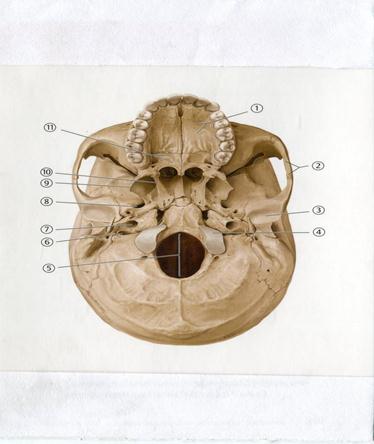

61. Төменде көрсетілген суреттегі белгіленген №5 анатомиялық құрылымды атаңыз.

А.Мойындырық тесігі

В.Таңдай өсіндісі

C. Таңдай сүйегі

D. Төменгі жақ шүңқыры

+E. Үлкен тесік